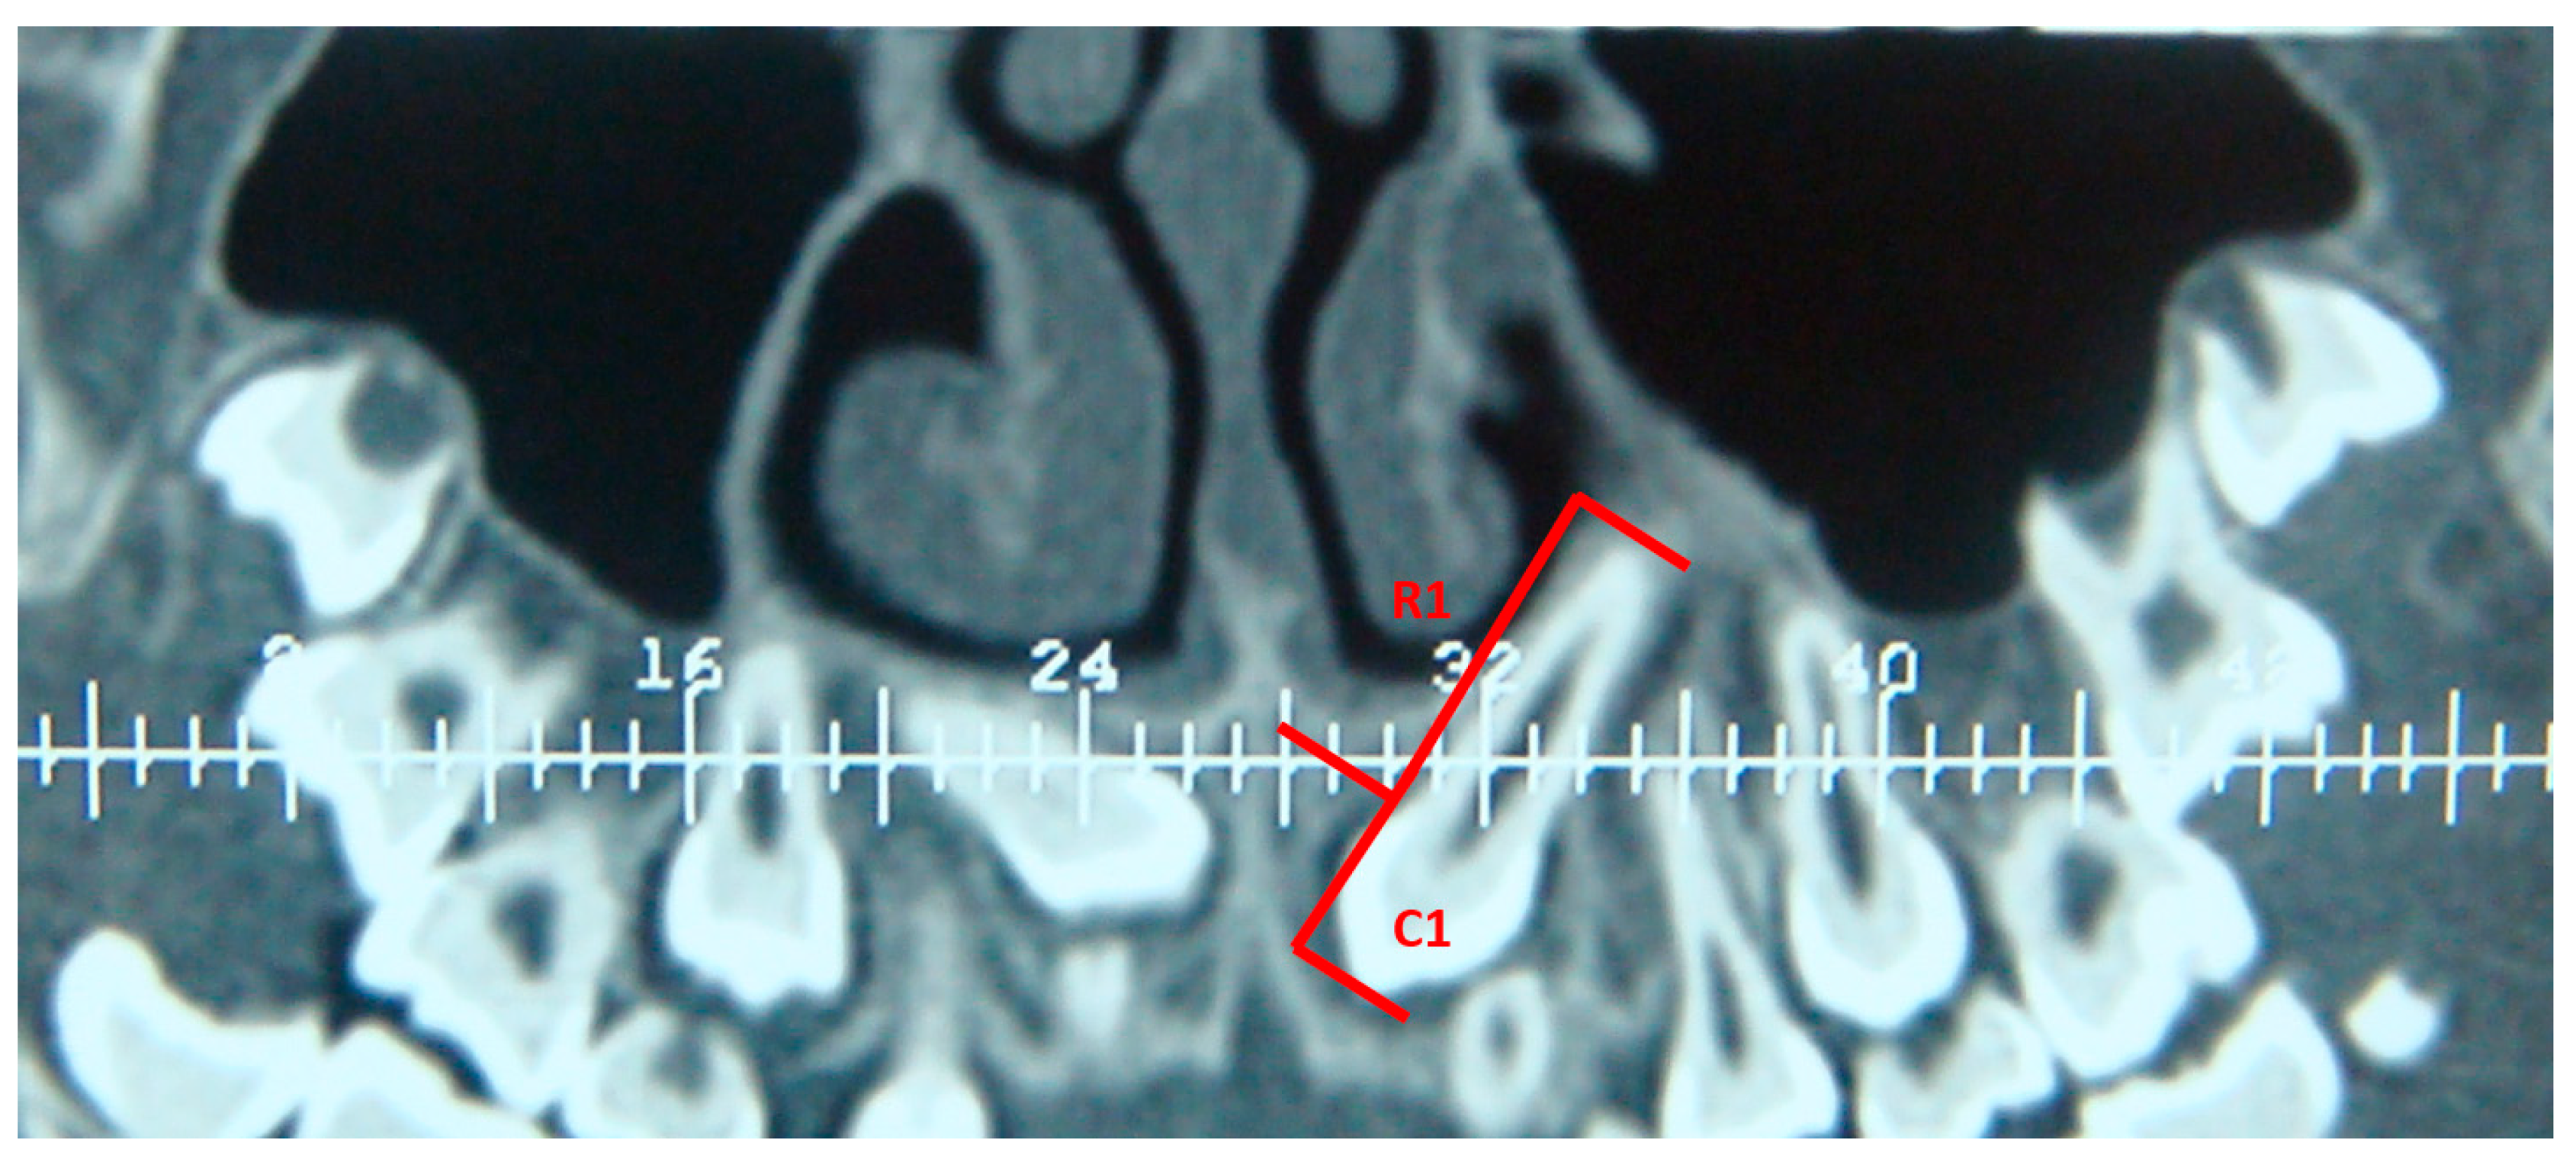

Measurements on CBCTs were taken by the same examiner, assessed in millimeters, and rounded up to the nearest 0.01 mm. Before proceeding with the measurements, the examiner detected the long axis of the tooth on the radiographs before (T0) and after treatment (T1). On CBCTs, three points were individualized on the long axis of the tooth: (1) apex; (2) cement-enamel junction; (3) occlusal plane. In this way, the root length (the distance between the apex and the cement–enamel junction) and the crown length (the distance between the cement–enamel junction and the occlusal plane) were obtained (Figure 1).

Figure 1. Cropped CBCT of the impacted upper left canine pre-treatment. C1, crown length before treatment; R1, root length before treatment.